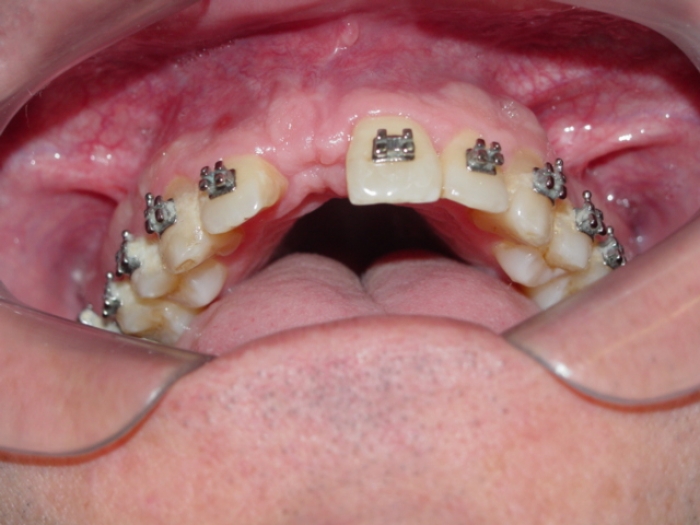

Imagem após enxerto ósseo